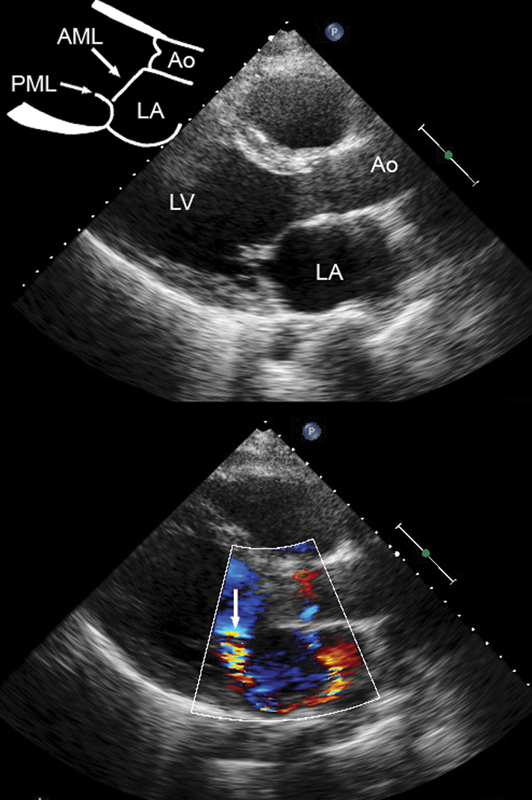

فحوصات تشخيصية لبعض امراض القلب والشرايين التاجية